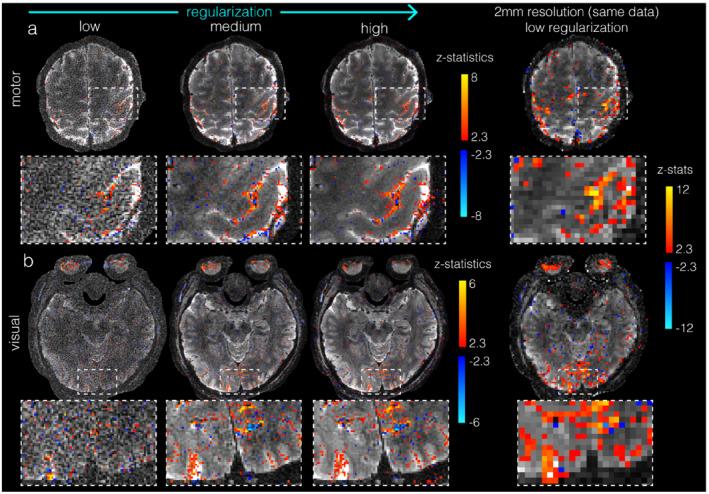

An improved, completely self-navigated version of the TURBINE sampling scheme was designed for fMRI at 7 Telsa. To demonstrate the image quality and spatial specificity of the acquisition, thin-slab visual and motor BOLD fMRI at 0.67 mm isotropic resolution (16 mm slab, TRvol = 2.32 s), and 0.8 × 0.8 × 2.0 mm (whole-brain, TRvol = 2.4 s) data were acquired. To prioritize the high spatial fidelity, we employed a temporally regularized reconstruction to improve sensitivity without any spatial bias.

RESULTS

TURBINE images provide high structural fidelity with almost no distortion, dropout, or T * blurring for the thin-slab acquisitions compared to conventional 3D EPI owing to the radial sampling in-plane and the short echo train used. This results in activation that can be localized to pre- and postcentral gyri in a motor task, for example, with excellent correspondence to brain structure measured by a T -MPRAGE. The benefits of TURBINE (low distortion, dropout, blurring) are reduced for the whole-brain acquisition due to the longer EPI train. We demonstrate robust BOLD activation at 0.67 mm isotropic resolution (thin-slab) and also anisotropic 0.8 × 0.8 × 2.0 mm (whole-brain) acquisitions.

方法

为在 7T 下进行 fMRI,设计了一种改进的、完全自我导航的 TURBINE 采样方案。为了展示采集的图像质量和空间特异性,我们在 0.67 毫米各向同性分辨率(16 毫米片层,TRvol = 2.32 秒)下进行了薄切片视觉和运动 BOLD fMRI,以及 0.8×0.8×2.0 毫米(全脑,TRvol = 2.4 秒)数据采集。为了优先考虑高空间保真度,我们采用了时间正则化重建来提高灵敏度,而没有任何空间偏差。

结果

与传统的 3D EPI 相比,TURBINE 图像提供了几乎没有失真、缺失或 T * 模糊的高结构保真度,这是由于在平面内进行的径向采样和使用的短回波链。这导致例如在运动任务中,可以将激活定位到中央前回和中央后回,与 T -MPRAGE 测量的大脑结构具有极好的对应关系。由于 EPI 链较长,TURBINE(低失真、缺失、模糊)的优势对于全脑采集会降低。我们在 0.67 毫米各向同性分辨率(薄片)下证明了稳健的 BOLD 激活,并且还在各向异性 0.8×0.8×2.0 毫米(全脑)采集下证明了稳健的 BOLD 激活。